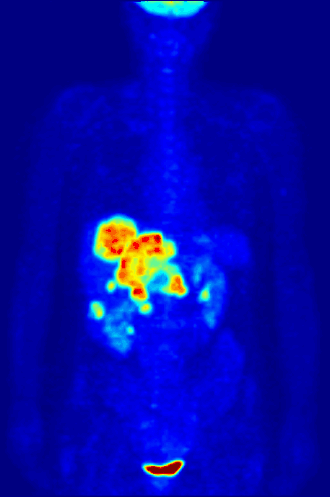

La TEP repose sur le principe général de la scintigraphie qui consiste à injecter un traceur dont on connaît le comportement et les propriétés biologiques pour obtenir une image du fonctionnement d'un organe ou la présence d'une cible moléculaire. Ce traceur est marqué par un atome radioactif (carbone, fluor, azote, oxygène, etc.) qui émet des positons dont l'annihilation produit deux photons. C'est la détection en coïncidence de ces photons qui permet la localisation de leur site d’émission et donc la concentration du traceur en chaque point de l'organe. C'est cette information quantitative que l'on représente sous la forme d'une image faisant apparaître en couleurs les zones de forte concentration du traceur.

Ainsi, la TEP permet de visualiser les activités du métabolisme des cellules : on parle d'imagerie fonctionnelle par opposition aux techniques d'imagerie dite structurelle comme celles basées sur les rayons X (radiologie ou CT-scan scanner) qui réalisent des images de l'anatomie. Par conséquent, la tomographie par émission de positons est un outil diagnostique qui permet de déceler certaines pathologies qui se traduisent par une altération de la physiologie normale comme les cancers, mais aussi les démences par exemple.

Les cellules cancéreuses se multiplient sans cesse. Ces nombreuses multiplications nécessitent beaucoup d’énergie ; elles ont donc une consommation anormalement élevée de glucose par rapport aux cellules normales. C’est grâce à cette consommation excessive de glucose que l’on peut repérer le tissu cancéreux avec la caméra TEP.

Le 18F-FDG se comporte comme le glucose, mais contrairement à celui-ci, il n’est pas une source d’énergie utilisable par la cellule cancéreuse. La molécule de 18F-FDG est phosphorylée par la cellule après son entrée ce qui l'empêche de ressortir de la cellule. Ensuite le FDG phosphorylé s'accumule dans le cytoplasme de la cellule car il n'est pas reconnu par les enzymes du cycle de dégradation du glucose normal. En devenant ainsi radioactive, la cellule émet des rayonnements qui peuvent être détectés par la caméra TEP. Le tissu cancéreux est ainsi repéré grâce à l’accumulation du produit radioactif sous la forme d’une image d’hyperfixation.

Toutes les informations recueillies par la caméra TEP reposent sur la radioactivité repérée dans les tissus après l'injection du 18F-FDG au patient. Le système informatique relié à la caméra TEP produit des images en coupe et en trois dimensions des endroits du corps où le 18F-FDG s'est accumulé.

Cancérologie

La TEP associée avec l'injection d'un traceur, ici le fluorodésoxyglucose (FDG, FDG-PET), est utilisée en cancérologie. Ce traceur est très proche chimiquement du glucose et va donc aller se fixer sur les tissus possédant un métabolisme élevé, notamment le cœur, le cerveau et les cellules tumorales. Les cellules tumorales malignes présentent un hypermétabolisme glucidique et une surexpression des transporteurs de glucose (GLUT-1). Le traceur (glucose transformé) ne peut pas subir d’hydrolyse (glycolyse) et il s’accumule donc dans les cellules décrites ci-dessus. C’est pour cela que la TEP est particulièrement indiquée dans la recherche des tumeurs malignes. Il existe aussi une accumulation du FDG dans les cellules inflammatoires activées (notamment les granulomes).

Les appareils les plus performants permettent actuellement de détecter des structures tumorales de petites tailles de l’ordre de 5 mm. La TEP est un outil puissant en oncologie, surpassant en sensibilité et en spécificité (toutes deux supérieures à 90 %) les examens de radiologie conventionnels (IRM, scanner X, échographie) dans de nombreux cancers. On peut citer par exemple, de façon non exhaustive, les lymphomes, les cancers et les nodules pulmonaires, les tumeurs des voies aérodigestives supérieures (bouche, larynx, pharynx), les localisations hépatiques des cancers digestifs, les mélanomes, les cancers du sein (en récidive) ou les cancers gynécologiques qui sont les principales indications de la TEP au FDG aujourd'hui[Quand ?].